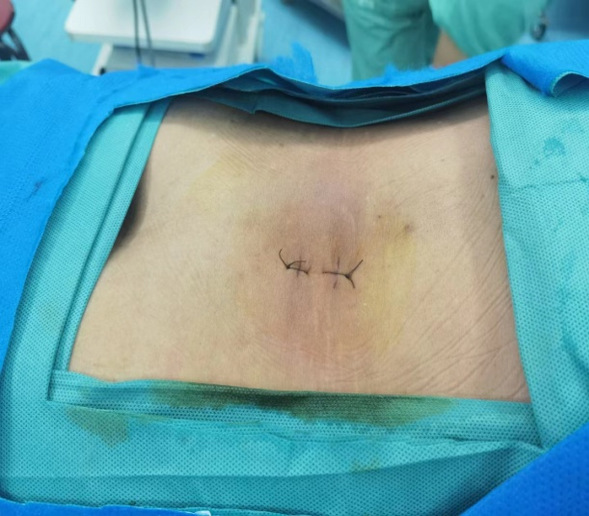

术中切口

手术是由负责人辛兆旭和助手赵越以及全体医生共同完成,创面只有两个1厘米的小切口。